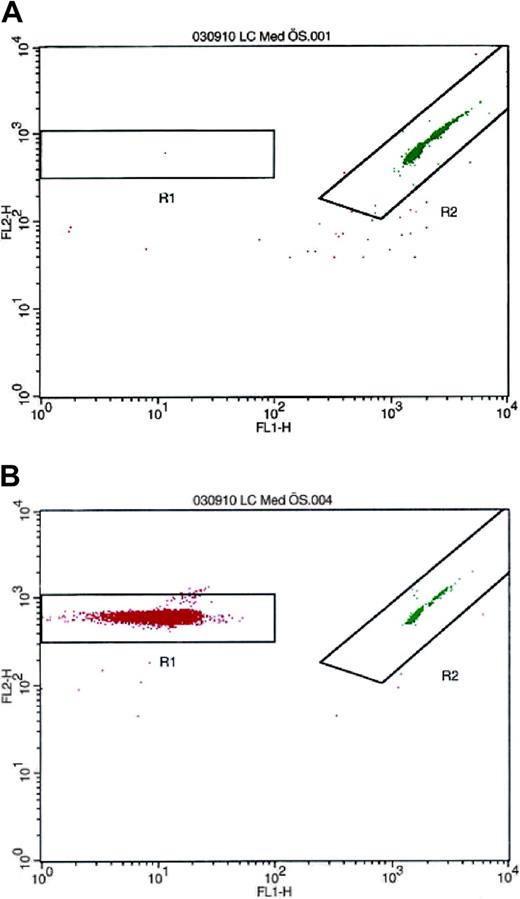

Because monocytes are known to synthesize PAI-1,24-26 separate experiments were performed to rule out the possibility that these cells could be the source of PAI-1 in the platelet suspension. To analyze the number of contaminating leukocytes, the isolated platelets were resuspended in platelet-free plasma to a concentration of 300 × 109/L. The PRP was analyzed by flow cytometry on a FACSCalibur (Becton Dickinson) with LeucoCOUNT according to the manufacturer's instructions. In these studies, the contamination rate was invariably fewer than 3 leukocytes in 10 million platelets (Figure 1).

Detection and enumeration of residual white blood cells in PRP with flow cytometry after LeucoCOUNT treatment. (A) PRP prepared by repeated centrifugation contained 2 to 3 contaminating leukocytes per 10 million platelets. (B) Buffy coat-contaminated PRP was used as positive control.

Detection and enumeration of residual white blood cells in PRP with flow cytometry after LeucoCOUNT treatment. (A) PRP prepared by repeated centrifugation contained 2 to 3 contaminating leukocytes per 10 million platelets. (B) Buffy coat-contaminated PRP was used as positive control.